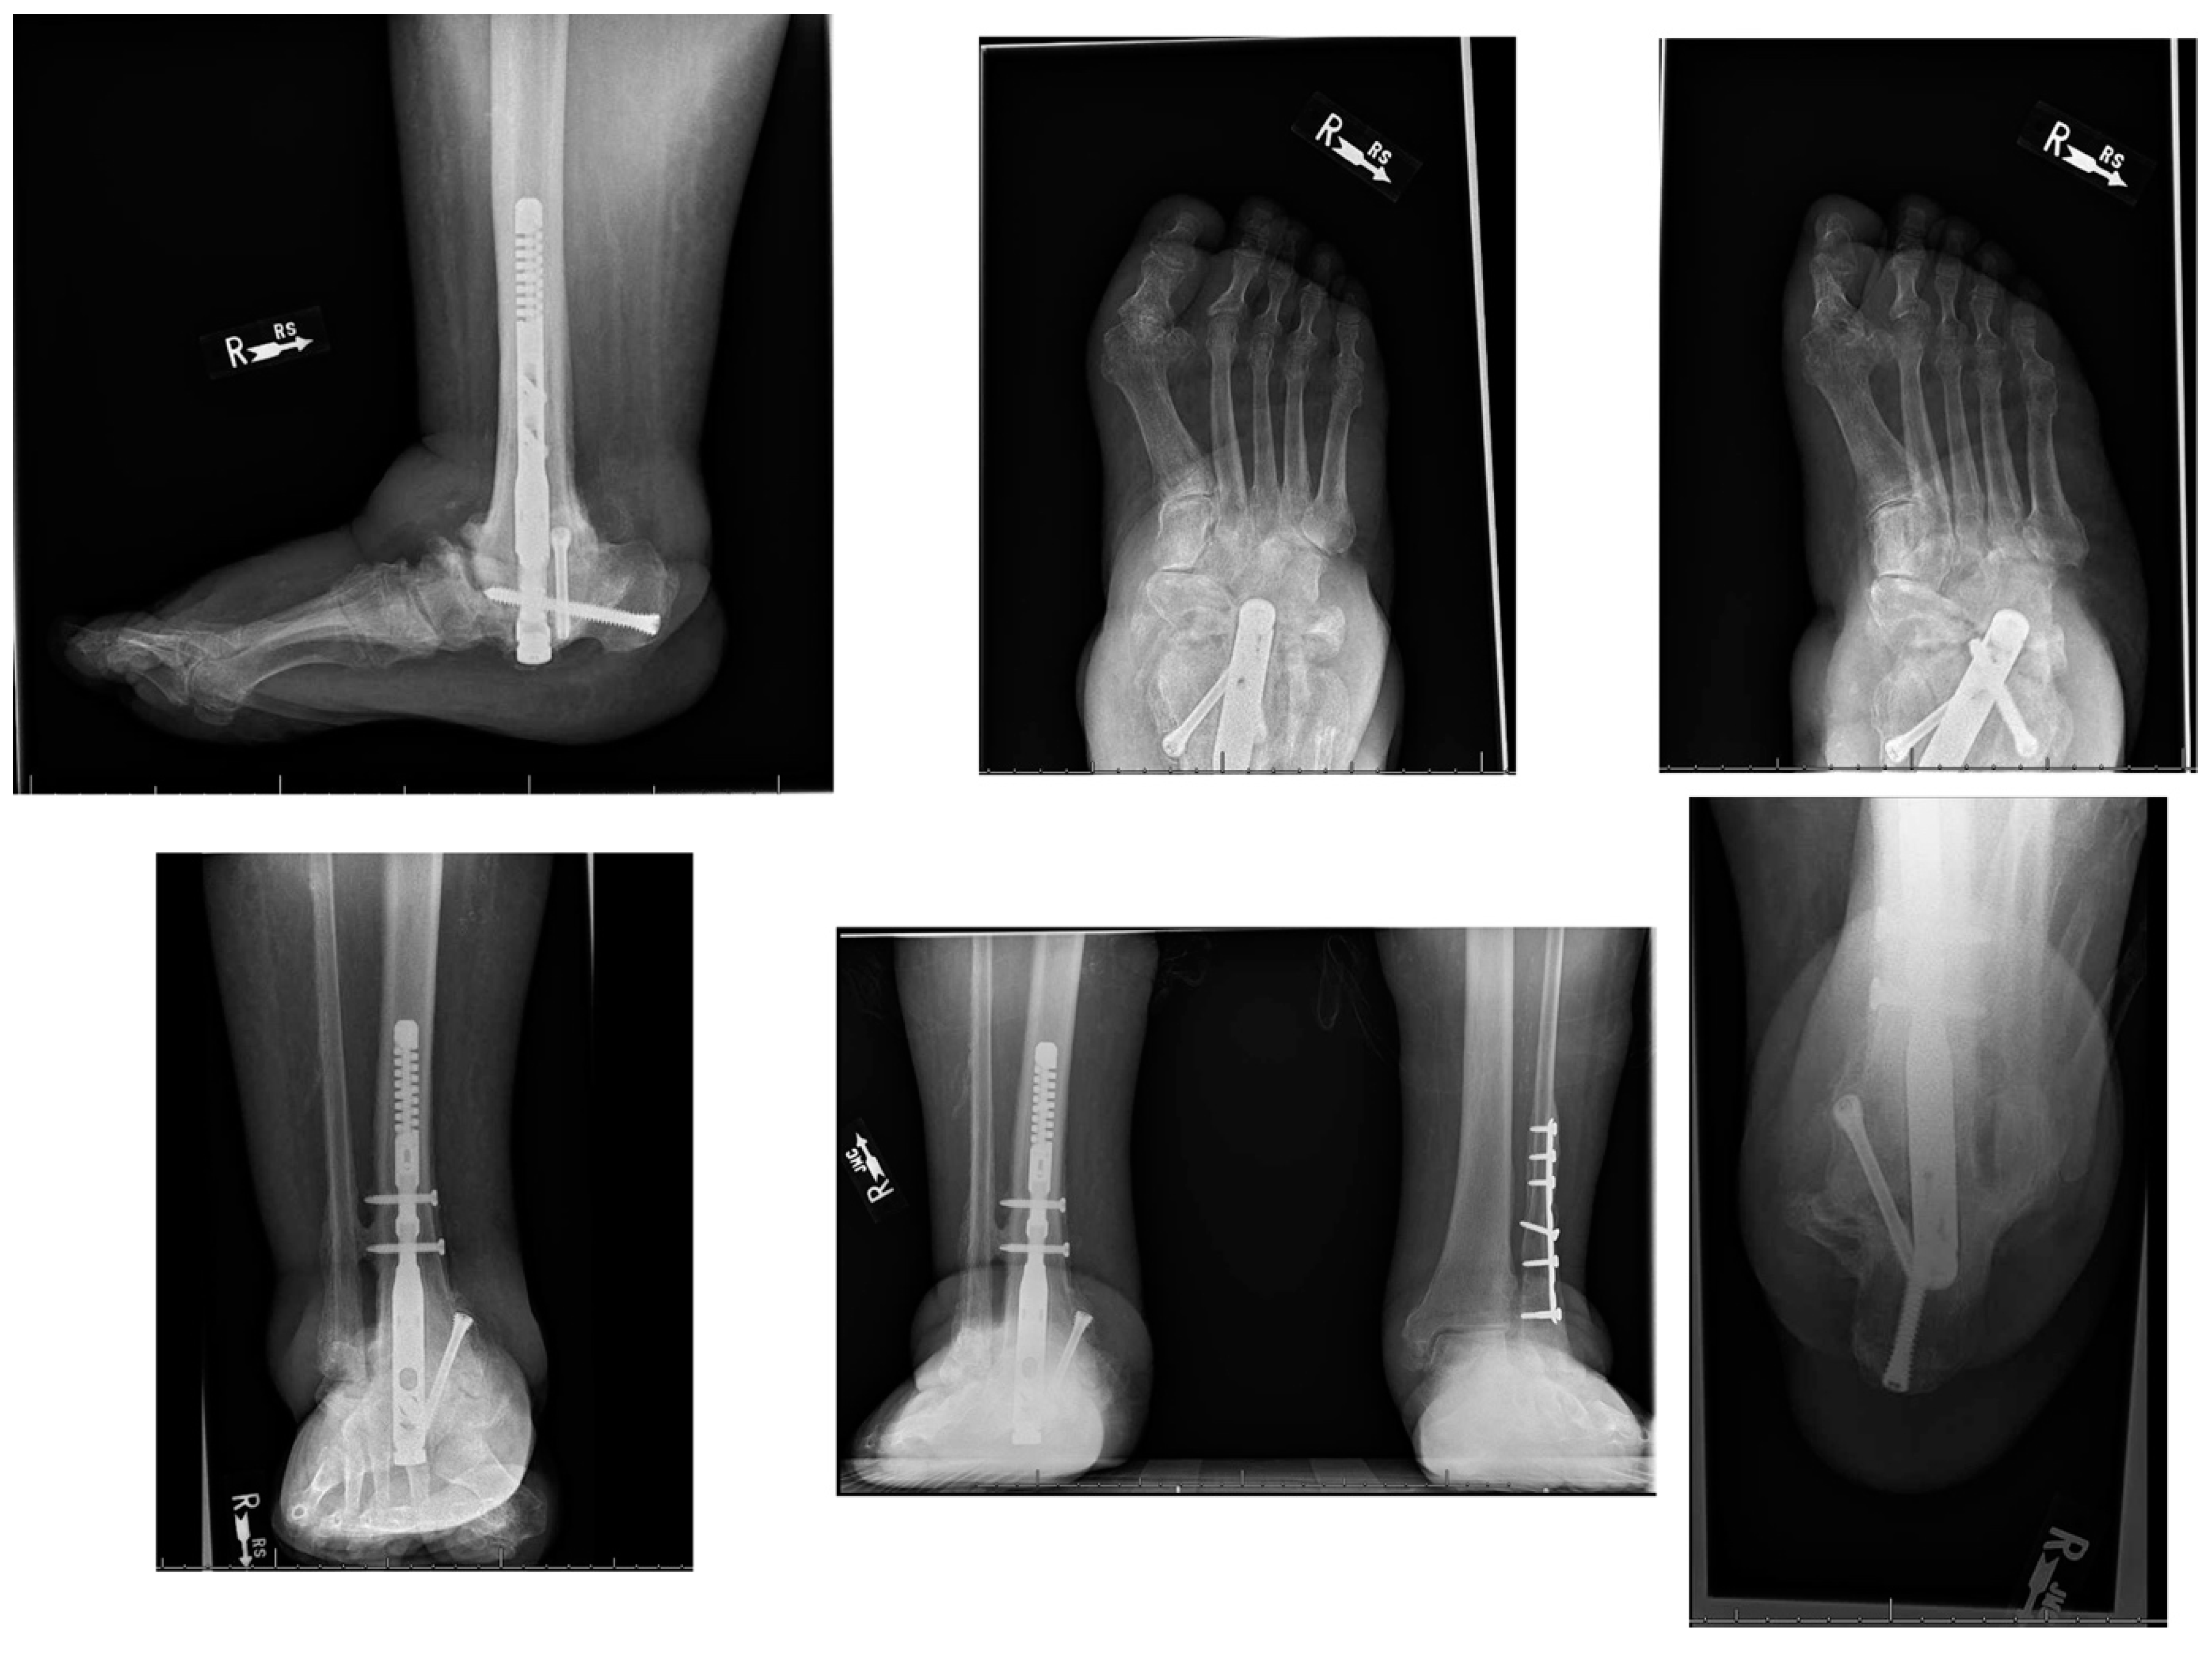

A 66-year-old morbidly obese African American female with a past medical history significant for congestive heart failure (CHF), uncontrolled type 2 diabetes mellitus (DM) with peripheral neuropathy, chronic stage 4 kidney disease (CKD), hyperlipidemia, hypertension (HTN), gastroesophageal reflux disease (GERD), obstructive sleep apnea (OSA), multiple joint arthritis, depression, and asthma, among other diagnoses, had presented to the emergency room with right foot pain and swelling for about two weeks. She was diagnosed with cellulitis of the foot and was sent to medicine service for management. The plain radiographs (Figure 1) showed talonavicular dislocation and marked degenerative changes consistent with Charcot arthropathy. She received intravenous (IV) antibiotics for three days and was discharged on oral antibiotics with instructions to follow up in orthopedic clinic. She returned to the emergency department two weeks later with fever and worsening symptoms of foot pain, accompanied by a draining medial hindfoot ulcer.

Figure 1. Preoperative radiographic images.